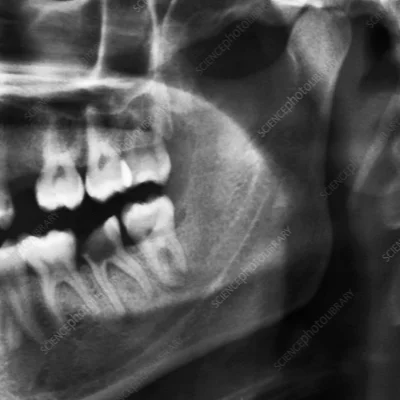

Jaw and TMJ Imaging

Diagnosing joint dysfunction or trauma.